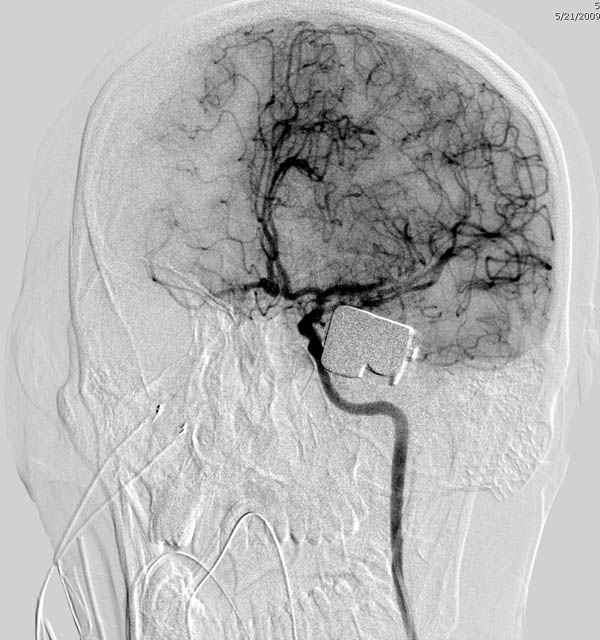

По протоколу сделаны все необходимые исследования: рентген, ангиограмма с 3Д реконструкцией, где обнаружили что все жизненно важные сосуды не задеты, даже некоторые "сидят" изгибаясь на ноже.

Одним махом нож удалить не удалось, пришлось раскачать и потом двумя руками удалили нож. Рана без кровотечения, обработана и зашита.